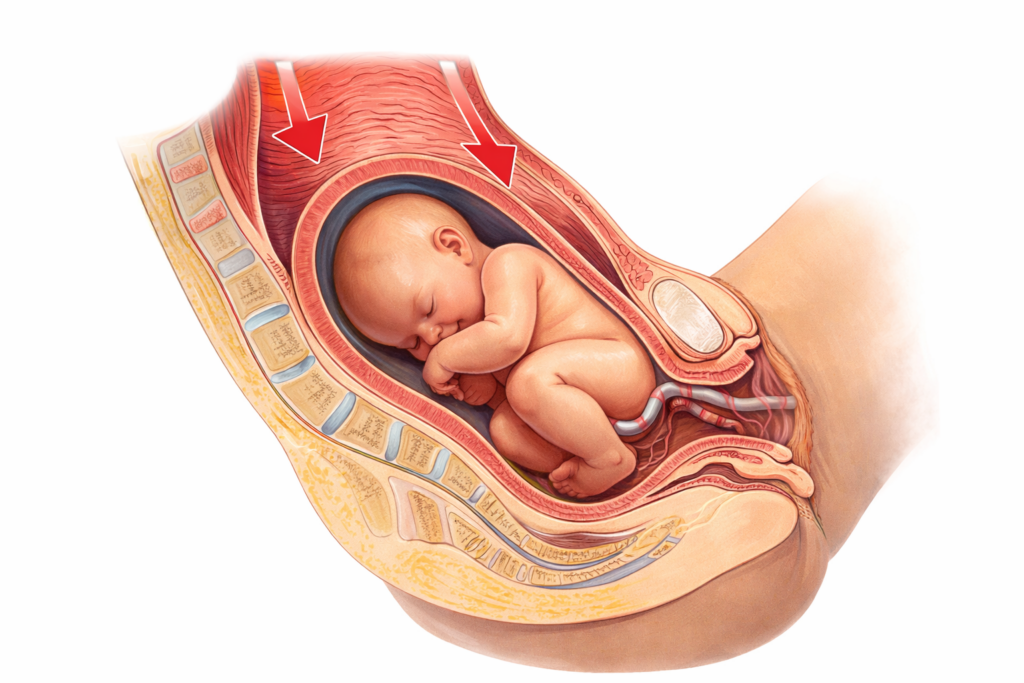

A Manobra de Kristeller é uma técnica obstétrica em que um profissional aplica pressão sobre o fundo do útero, ou seja, na parte superior da barriga da gestante, durante o período expulsivo do parto.

O objetivo seria empurrar o bebê para baixo, tentando acelerar a saída dele pelo canal de parto.

Durante o nascimento, o corpo da mulher trabalha em conjunto com as contrações uterinas e com o esforço voluntário de empurrar. Quando alguém pressiona o abdômen de fora para dentro, esse processo natural pode ser interrompido ou até mesmo prejudicado.

A Manobra de Kristeller geralmente ocorre durante o período expulsivo do parto.

É nessa fase que o corpo trabalha em conjunto com as contrações uterinas para ajudar o bebê a nascer.

Em um parto fisiológico, o bebê vai descendo gradualmente, guiado pelas contrações do útero e pelos movimentos naturais da mulher.

Durante a manobra, um profissional de saúde — geralmente médico ou enfermeiro — aplica pressão direta sobre o fundo do útero, que fica na parte superior da barriga da gestante.

A intenção é empurrar o bebê para baixo, na direção do canal de parto.

No entanto, o problema é que essa pressão externa não acompanha o ritmo natural das contrações, o que pode gerar um aumento súbito da pressão dentro do útero.

Quando alguém pressiona o abdômen da gestante durante o parto, ocorre um aumento súbito da pressão dentro do útero.

Essa pressão é transmitida diretamente ao bebê e às estruturas do canal de parto.

O problema é que o corpo da mulher já está trabalhando intensamente nesse momento.

- os tecidos do períneo estão se distendendo

Quando uma pressão externa é aplicada de forma abrupta, o corpo pode não conseguir responder de forma equilibrada.

Em vez de ajudar o nascimento, a manobra pode gerar tensão excessiva nos tecidos, aumentar o desconforto da mulher e interferir na dinâmica natural do parto.